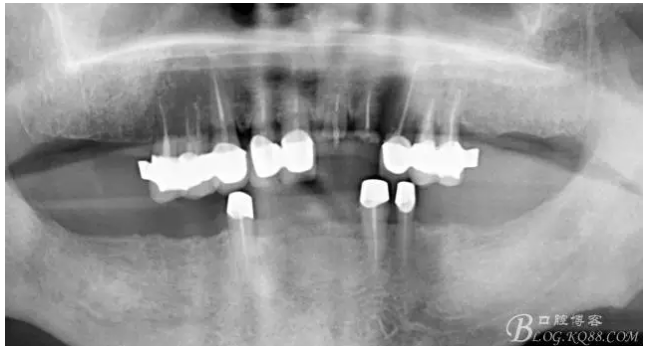

雖然牙根折斷了,但是從這張片子可以看出我們的套筒冠還是很堅(jiān)挺的,有牙齦的退縮,但是牙槽骨致密程度非常好,值得欣慰

最近復(fù)查的照片,牙周維護(hù)好一些了,畢竟是一個(gè)80歲的老爺爺了,每次來拄著拐,還要跟著很多人攙扶著過來很不容易了。